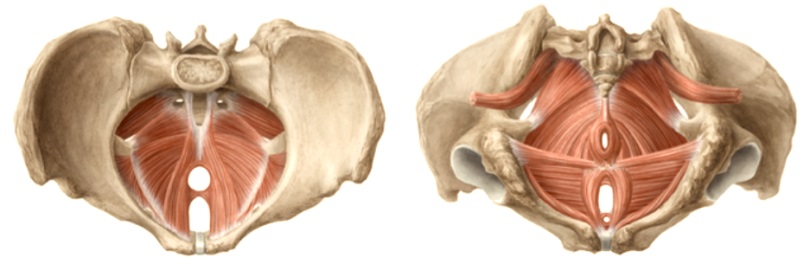

Γιατί όλες οι γυναίκες – αλλά και οι άνδρες – πρέπει να κάνουν ασκήσεις πυελικού εδάφους (ΠΕ) Το Πυελικό Έδαφος (Pelvic Floor) αποτελεί μια μυοσκελετική δομή του κορμού, που απαρτίζεται από συνδέσμους, περιτονίες και μια ομάδα σημαντικών γραμμωτών μυών. Αυτοί οι μύες ονομάζονται Μύες του Πυελικού Εδάφους (Pelvic Floor Muscles) και διαδραματίζουν σπουδαίο ρόλο στην […]